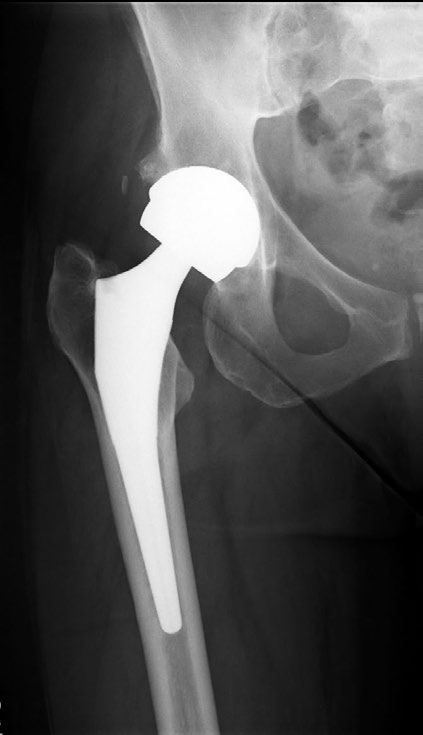

90-dnevna smrtnost nakon ugradnje proteze kuka

Rezultati velike retrospektivne analize u kojoj su obrađeni rezultati od 409.096 operacija ugradnje proteze kuka objavljeni su u časopisu The Lancet od 28. rujna 2013. godine. Navedene operacije izvedene su u razdoblju između travnja 2003. i prosinca 2011., a rezultati su ekstrahirani iz državnih registara Engleske i Walesa. Primarna dijagnoza kod svih pacijenata bio je osteoartritis kuka. Od ukupnog broja pacijenata, 1743 su umrla u razdoblju od 90 dana nakon operacije. Rezultati su pokazali kako se mortalitet s godinama smanjivao pa je tako 2003. godine iznosio 0,56% a 2011. 0,29%. Nekoliko se faktora povezuje sa smanjenim mortalitetom, a to su: stražnji pristup pri operaciji, mehanička tromboprofilaksa, medikamentozna tromboprofilaksa heparinom s aspirinom ili bez njega, spinalna umjesto opće anestezije te iznenađujuće, prekomjerna tjelesna težina. Tip proteze nije imao utjecaj na mortalitet. U konačnici autori zaključuju da bi se smrtnost mogla dalje sniziti kada bi se u svim centrima provodile mjere medikamentozne i mehaničke tromboprofilakse, stražnji kirurški pristup te spinalna umjesto opće anestezije. |